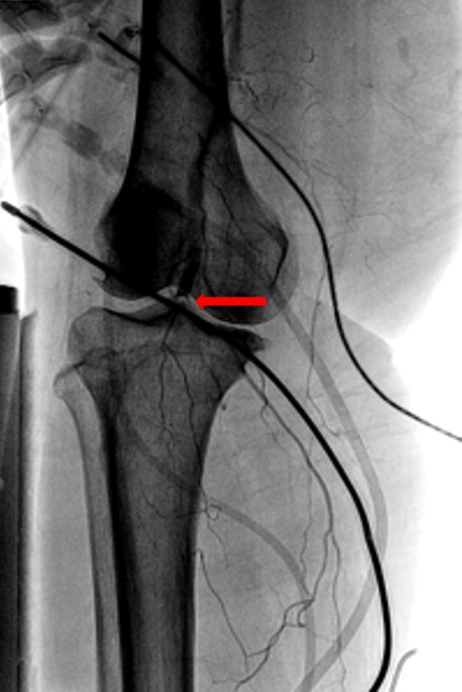

Rate control was achieved with diltiazem infusion and anticoagulation with intravenous heparin was initiated. Echocardiogram showed a left atrial mass adjacent to the interatrial septum suspicious for atrial myxoma (Figure 1). Computed tomography scan showed a left atrial filling defect that enhanced with contrast and measured 4.5x3.3x4.4 cm (Figure 2) as well as a filling defect in the superior mesenteric artery (Figure 3). Lower extremity angiogram demonstrated abrupt cessation of flow consistent with an embolus to the right popliteal artery (Figure 4) and a patent left popliteal artery. Right popliteal arterial thrombectomy was performed. The patient then underwent excision of the left atrial mass. Maze procedure and left atrial appendage ligation. The examination of excised mass revealed an organized thrombus (Figure 5). The postoperative course was uneventful and the patient was discharged on warfarin and metoprolol.

Figure 4: Lower extremity arteriogram showing abrupt cessation of flow in the right popliteal artery (arrow).